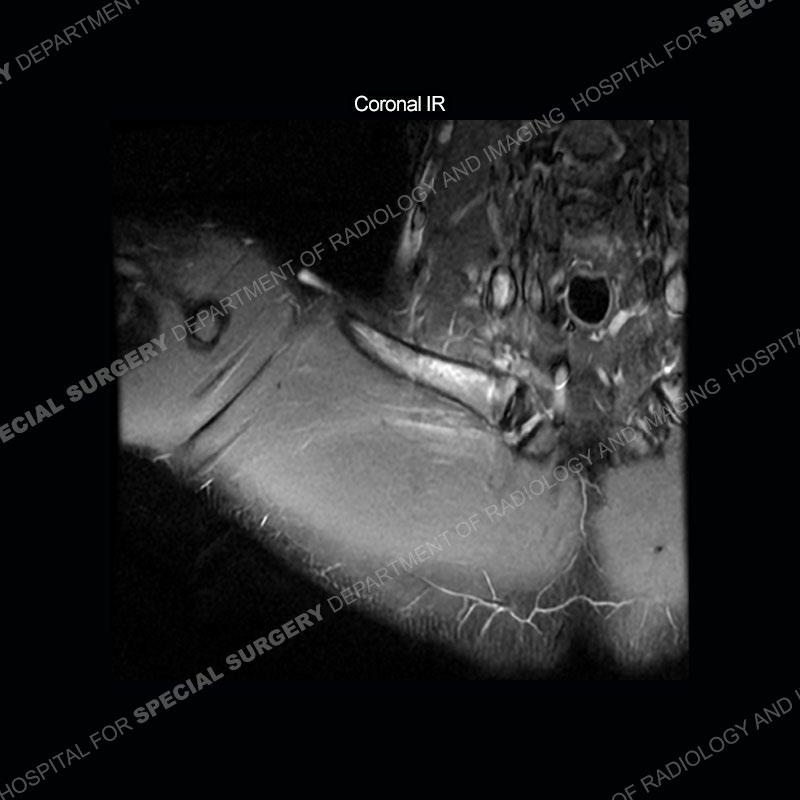

The initial MRI of the shoulder shows marked marrow edema pattern of the clavicle and marked edema/hematoma of the subclavius muscle. Given the pathology extending outside of the normal field of view, the exam was extended for further coverage than typical on the axial IR and axial PD images.

Subsequent imaging of the chest shows disruption of tissue along the medial aspect of the right clavicle and a deep insinuation of the bone along the medial aspect of the right clavicle. This is made more conspicuous with comparison to the left side. The edema pattern of the clavicle and the edema/hematoma of the subclavius persist.